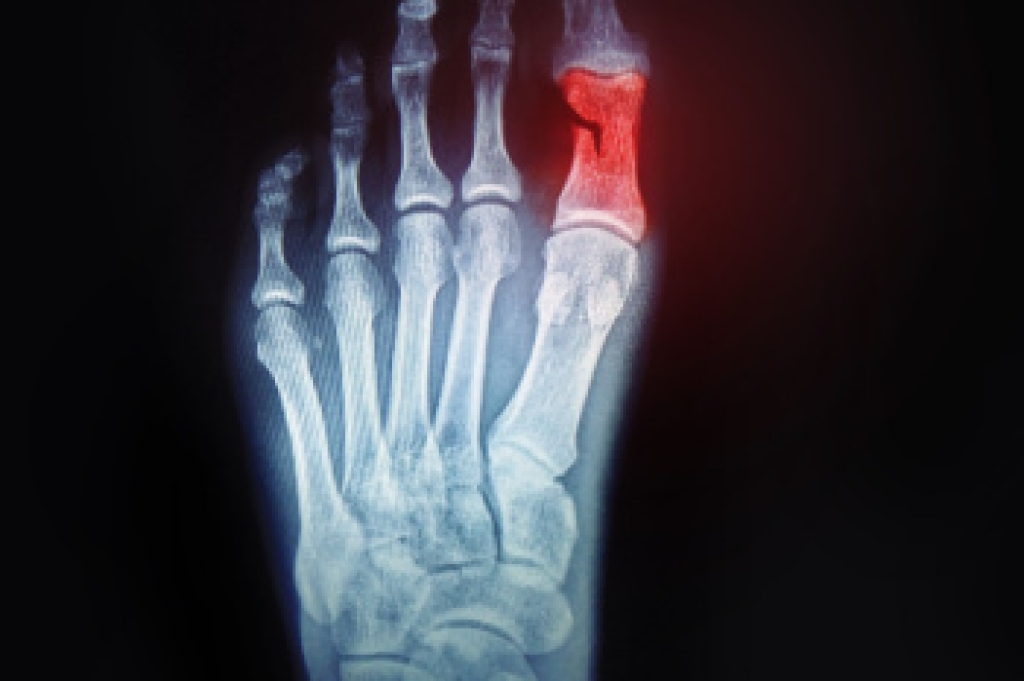

Identifying a broken toe is important for timely treatment and recovery. One of the primary signs is a noticeable change in the toe's shape, as it may appear misaligned, crooked, or deformed. Severe pain is another common indicator, often sharp and intense at the moment of injury and persisting with movement. The affected toe might also show swelling and bruising, with discoloration appearing as a dark purple or blue hue. In some cases, there may be difficulty or discomfort when trying to move the toe. Prompt medical evaluation is essential for proper diagnosis and treatment, which may include rest, immobilization, or in severe cases, surgical intervention. If you have broken your toe, it is suggested that you consult a podiatrist who can offer you the correct treatment.

What to Know About a Broken Toe

Although most people try to avoid foot trauma such as banging, stubbing, or dropping heavy objects on their feet, the unfortunate fact is that it is a common occurrence. Given the fact that toes are positioned in front of the feet, they typically sustain the brunt of such trauma. When trauma occurs to a toe, the result can be a painful break (fracture).

Symptoms of a Broken Toe

- Throbbing pain

- Swelling

- Bruising on the skin and toenail

- The inability to move the toe

- Toe appears crooked or disfigured

- Tingling or numbness in the toe

Generally, it is best to stay off of the injured toe with the affected foot elevated.

Severe toe fractures may be treated with a splint, cast, and in some cases, minor surgery. Due to its position and the pressure it endures with daily activity, future complications can occur if the big toe is not properly treated.